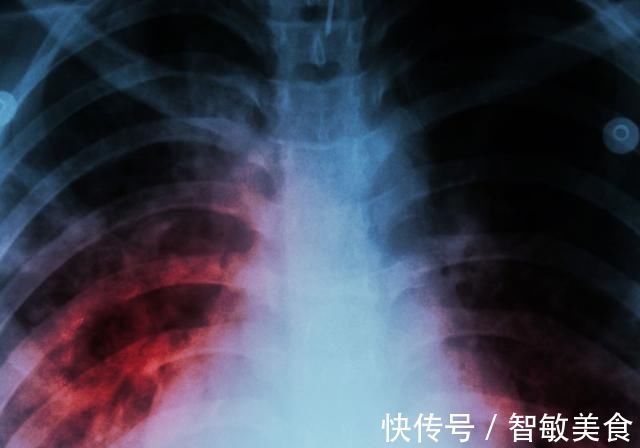

肺结节|查出肺结节,担心是肺癌若是这2种情况,先放宽心

体检查出了肺结节,有可能是肺癌发出的警告。因为部分肺结节存在恶化这种情况,有可能在确定肺结节之后通过性质的判断发现有癌细胞存在,这种情况说明具备了肺癌的趋势,应该通过积极配合治疗的方式来控制疾病发展,避免肺癌出现。当然也并非所有的肺结节都是肺癌,病人应该根据结节的性质以及具体情况综合判断。

有部分情况下的肺结节其实并不需要担心,特别是体积非常小,而且经过长时间的观察并没有特殊改变的肺结节,这种情况性质稳定,而且也没有恶化这种趋势,可以排除成为肺癌的可能。

部分情况的肺结节没有癌变的表现,不需要太过紧张,特别是那些结节表面较光滑,没有周围模糊,出现特殊形状的结节,这种情况出现恶化的可能性较低。

一般具备恶化特点的肺结节形状都比较特殊,而且结节的边缘会出现模糊或者形状的改变。身体没有这种情况,肺结节边缘光滑,而且性质稳定,保守处理即可。

由此可见,体检出了肺结节确实有可能是肺癌,但是要判断其性质,还应该综合结节的形态、性质等进行判断,不要过度紧张,否则检查出了肺结节过度担忧,可能会带来其他方面的影响。值得一提的是,如果发现肺结节是肺癌引起,病人需要马上治疗,早治疗预后良好,可以通过手术的方式切除病灶,术后身体护理工作过好,可以避免肺部功能持续下降带来伤害。